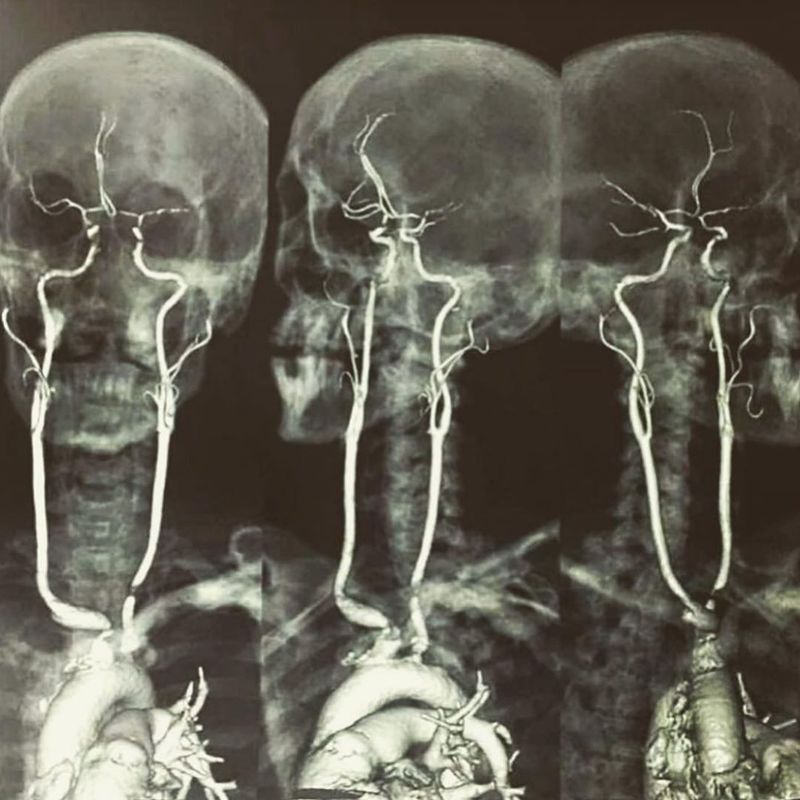

Here is an amazing shot showing contrasted MRI displaying the origin & length of the carotid arteries. The carotid arteries are major blood vessels in the neck that supply blood to the brain, neck, and face. There are two carotid arteries, one on the right and one on the left. In the neck, each carotid artery branches into two divisions, internal & external carotid arteries.